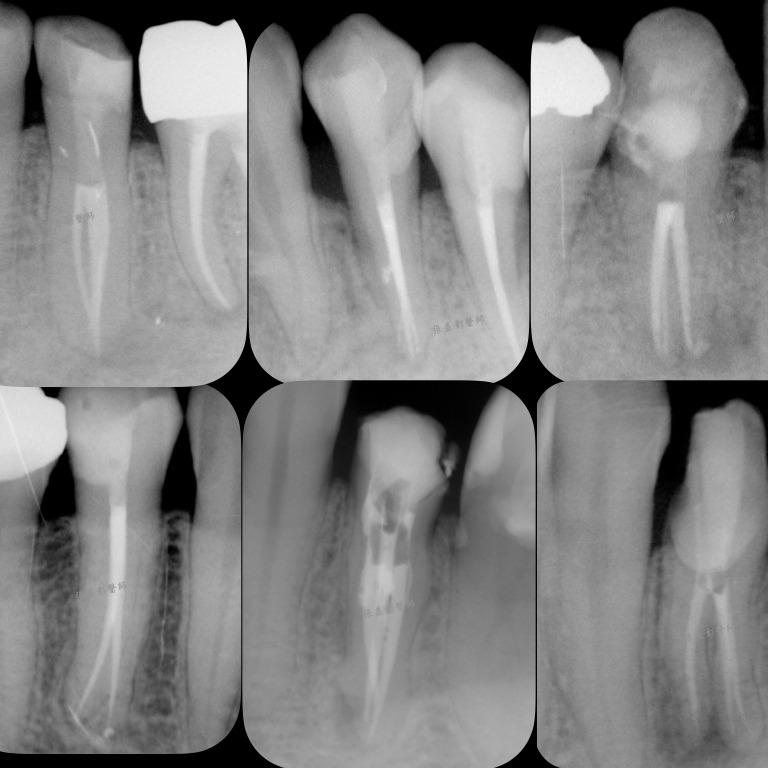

張益彰醫師 | 衛福部定牙髓病專科

多根管小臼齒

側根管